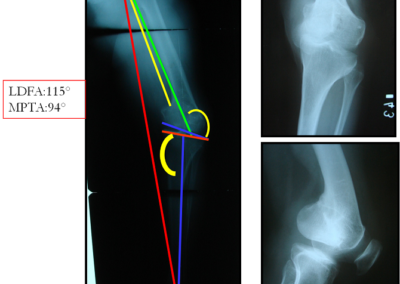

arthritis deformity surgery endoprosthesis hip prosthesis ilizarov ilizarov surgery infected nonunion knee prosthesis lengthening surgery limb lengthening surgery nonunion periprosthetic infection psodoartroz revision surgery total hip prosthesis total knee prosthesis